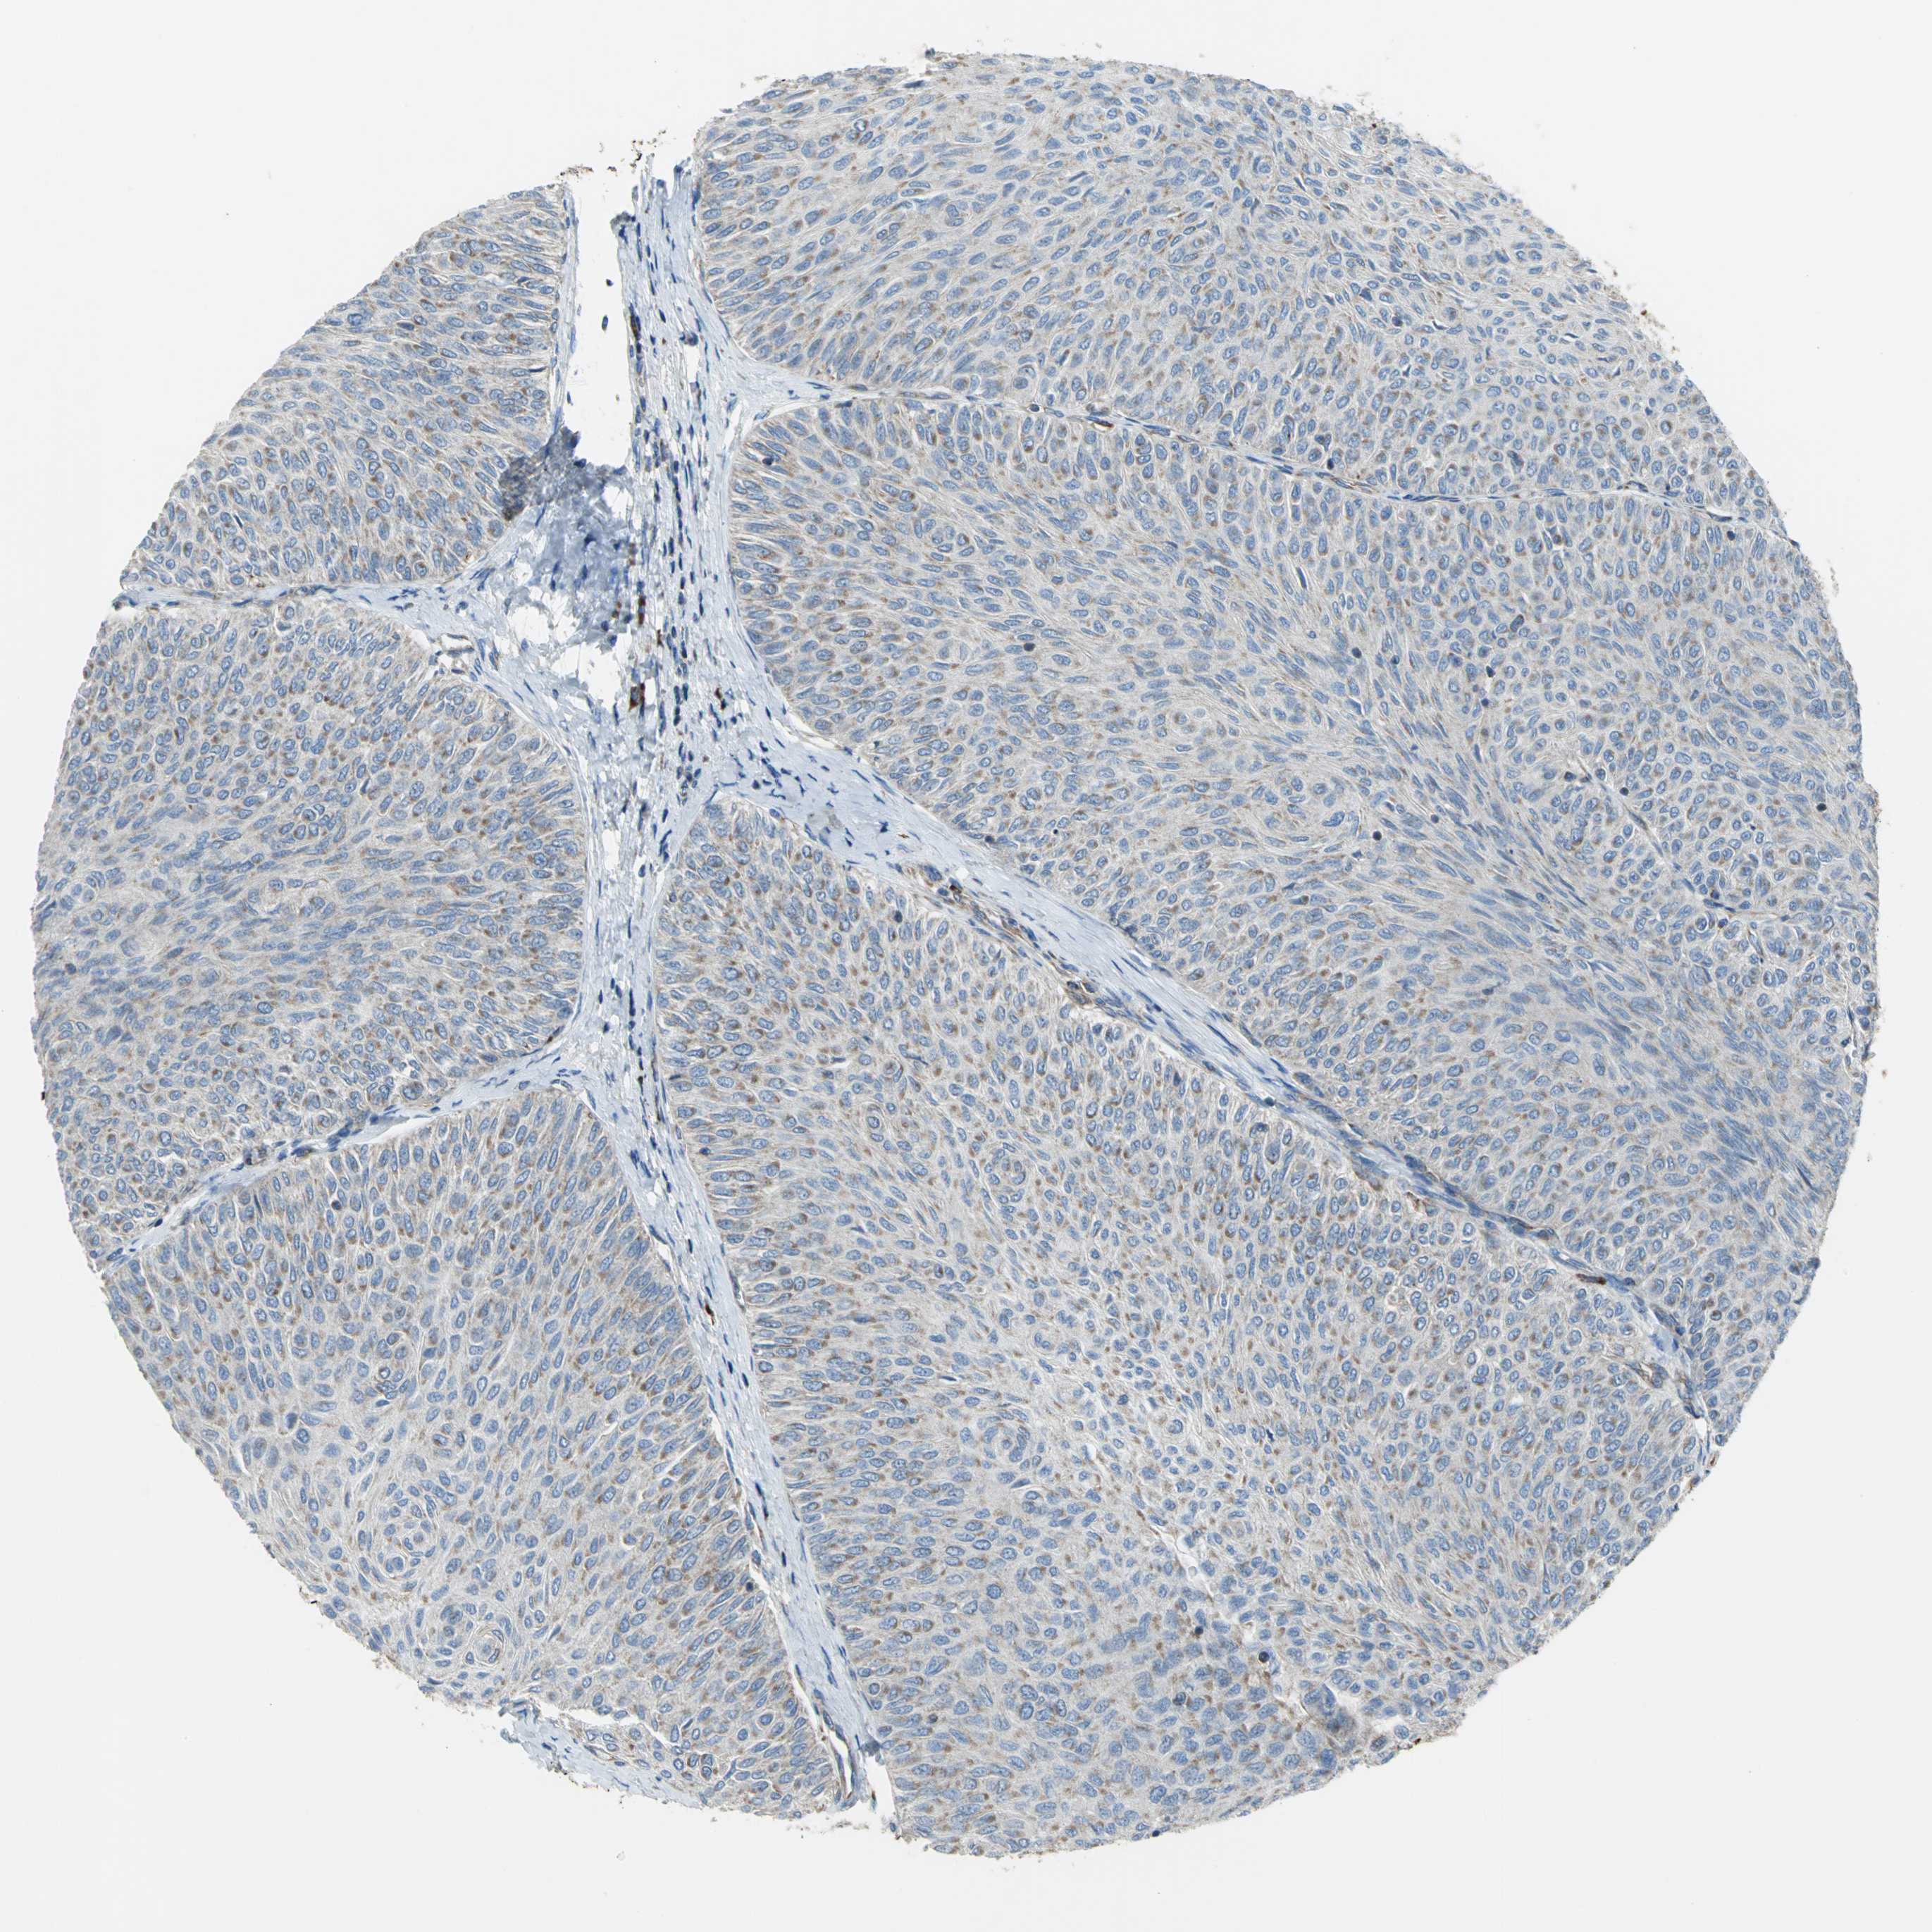

UROTHELIAL CANCER - Protein expressioni

A mouse-over function shows sample information and annotation data. Click on an image to view it in a full screen mode. Samples can be filtered based on level of antibody staining by selecting one or several of the following categories: high, medium, low and not detected. The assay and annotation is described here.

Note that samples used for immunohistochemistry by the Human Protein Atlas do not correspond to samples in the TCGA dataset.

Antibody stainingi

Antibody staining in the annotated cell types in the current human tissue is reported as not detected, low, medium, or high, based on conventional immunohistochemistry profiling in selected tissues. This score is based on the combination of the staining intensity and fraction of stained cells.

Each image is clickable and will lead to virtual microscopy that enables deeper exploration of all samples and also displays staining intensity scores, fraction scores and subcellular localization as well as patient and tissue information for each sample.

Antibody HPA005445

Staining

High

Medium

Low

Not detected

Intensity

Strong

Moderate

Weak

Negative

Quantity

>75%

75%-25%

<25%

None

Location

Nuclear

Cytoplasmic/membranous

Cytoplasmic/membranous,nuclear

Urothelial carcinoma, High grade

Urothelial carcinoma, Low grade